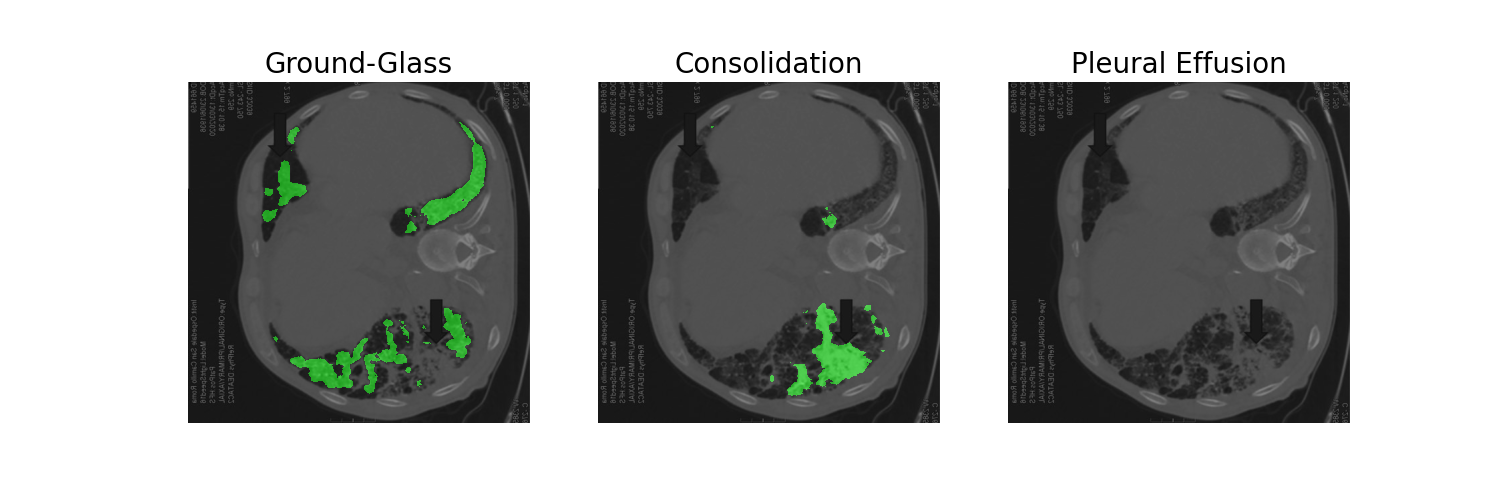

The following is an AI medical segmentation tool for detecting ground-glass, consolidation and pleural effusion in patient lung CT scans. Some reports have shown that ground-glass/consolidation measurements can further enhance the prognosis estimation for Covid-19 patients.

For the front-end, we have used anvil which is a python-based platform to build our very own app. The platform provided us with a mechanism to build a rapid and working prototype of our idea. For our backend-server, we have deployed our deep learning model on a highly reliable AWS server using an EC2 instance. For the deep learning part, we trained a state-of-the-art U-SegNet model for medical segmentation using PyTorch.